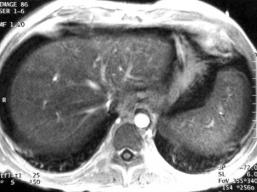

Ce patient, traité pour une

leucémie, est adréssé pour dégradation de sa

fonction hépatique et l'appartion récente d'une ascite. L'échographie

ne montre pas de thrombose des veines sus hépatiques on suspecte

une maladie veinoocclusive.

Après injection

de produit de contraste il y a une trop belle image portale. Les branches

portales distales sont anormalement opacifiées ce qui est tout a

fait cohérent avec le diagnostique de maladie veino-occlusive. Par

ailleur le foie est en hyposignal T1 par surchage en fer lié au

traitement chimiothérapique.